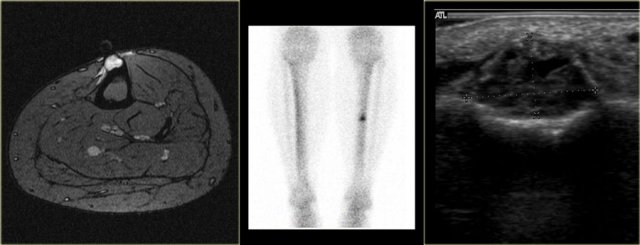

Chondroblastoma (9)

What are the findings:

• Well-defined osteolytic lesion in the talus.

• No matrix formation.

• Subtle reactive sclerosis.

• T2-WI with FS shows typical extensive peritumoral edema in the entire bone.

• High uptake on bone scintigraphy.

Diagnosis: Chondroblastoma.

The talar bone is one of the preferential sites for chondroblastoma.